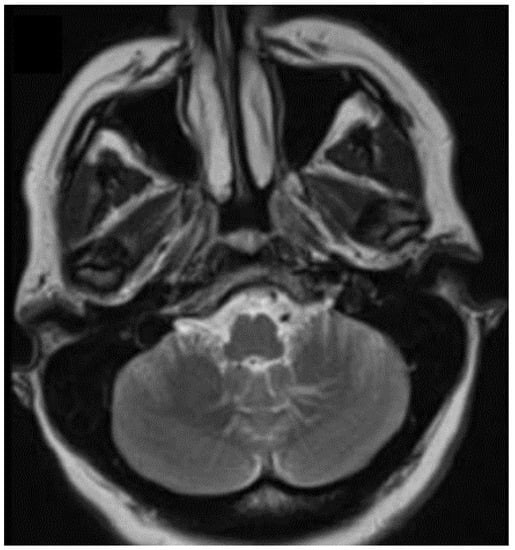

- Ebrahimzadeh, K.; Tavassol, H.H.; Mousavinejad, S.A.; Ansari, M.; Kazemi, R.; Bahrami-Motlagh, H.; Jalili Khoshnoud, R.; Sharifi, G.; Samadian, M.; Rezaei, O. The Sensorineural Hearing Loss Related to a Rare Infratentorial Developmental Venous Angioma: A Case Report and Review of Literature. J. Neurol. Surg. A Cent. Eur. Neurosurg. 2021. [Google Scholar] [CrossRef]

- Rosenblum, J.S.; Nazari, M.; Al-Khalili, Y.; Potigailo, V.; Veznedaroglu, E. Unilateral symptomatic hypertrophic olivary degeneration secondary to Midline brainstem cavernous angioma: A case report and review of the literature. World Neurosurg. 2018, 110, 294–300. [Google Scholar] [CrossRef] [PubMed]

- Rinaldo, L.; Lanzino, G.; Flemming, K.D.; Krings, T.; Brinjikji, W. Symptomatic Developmental Venous Anomalies. Acta Neurochir. 2020, 162, 1115–1125. [Google Scholar] [CrossRef]